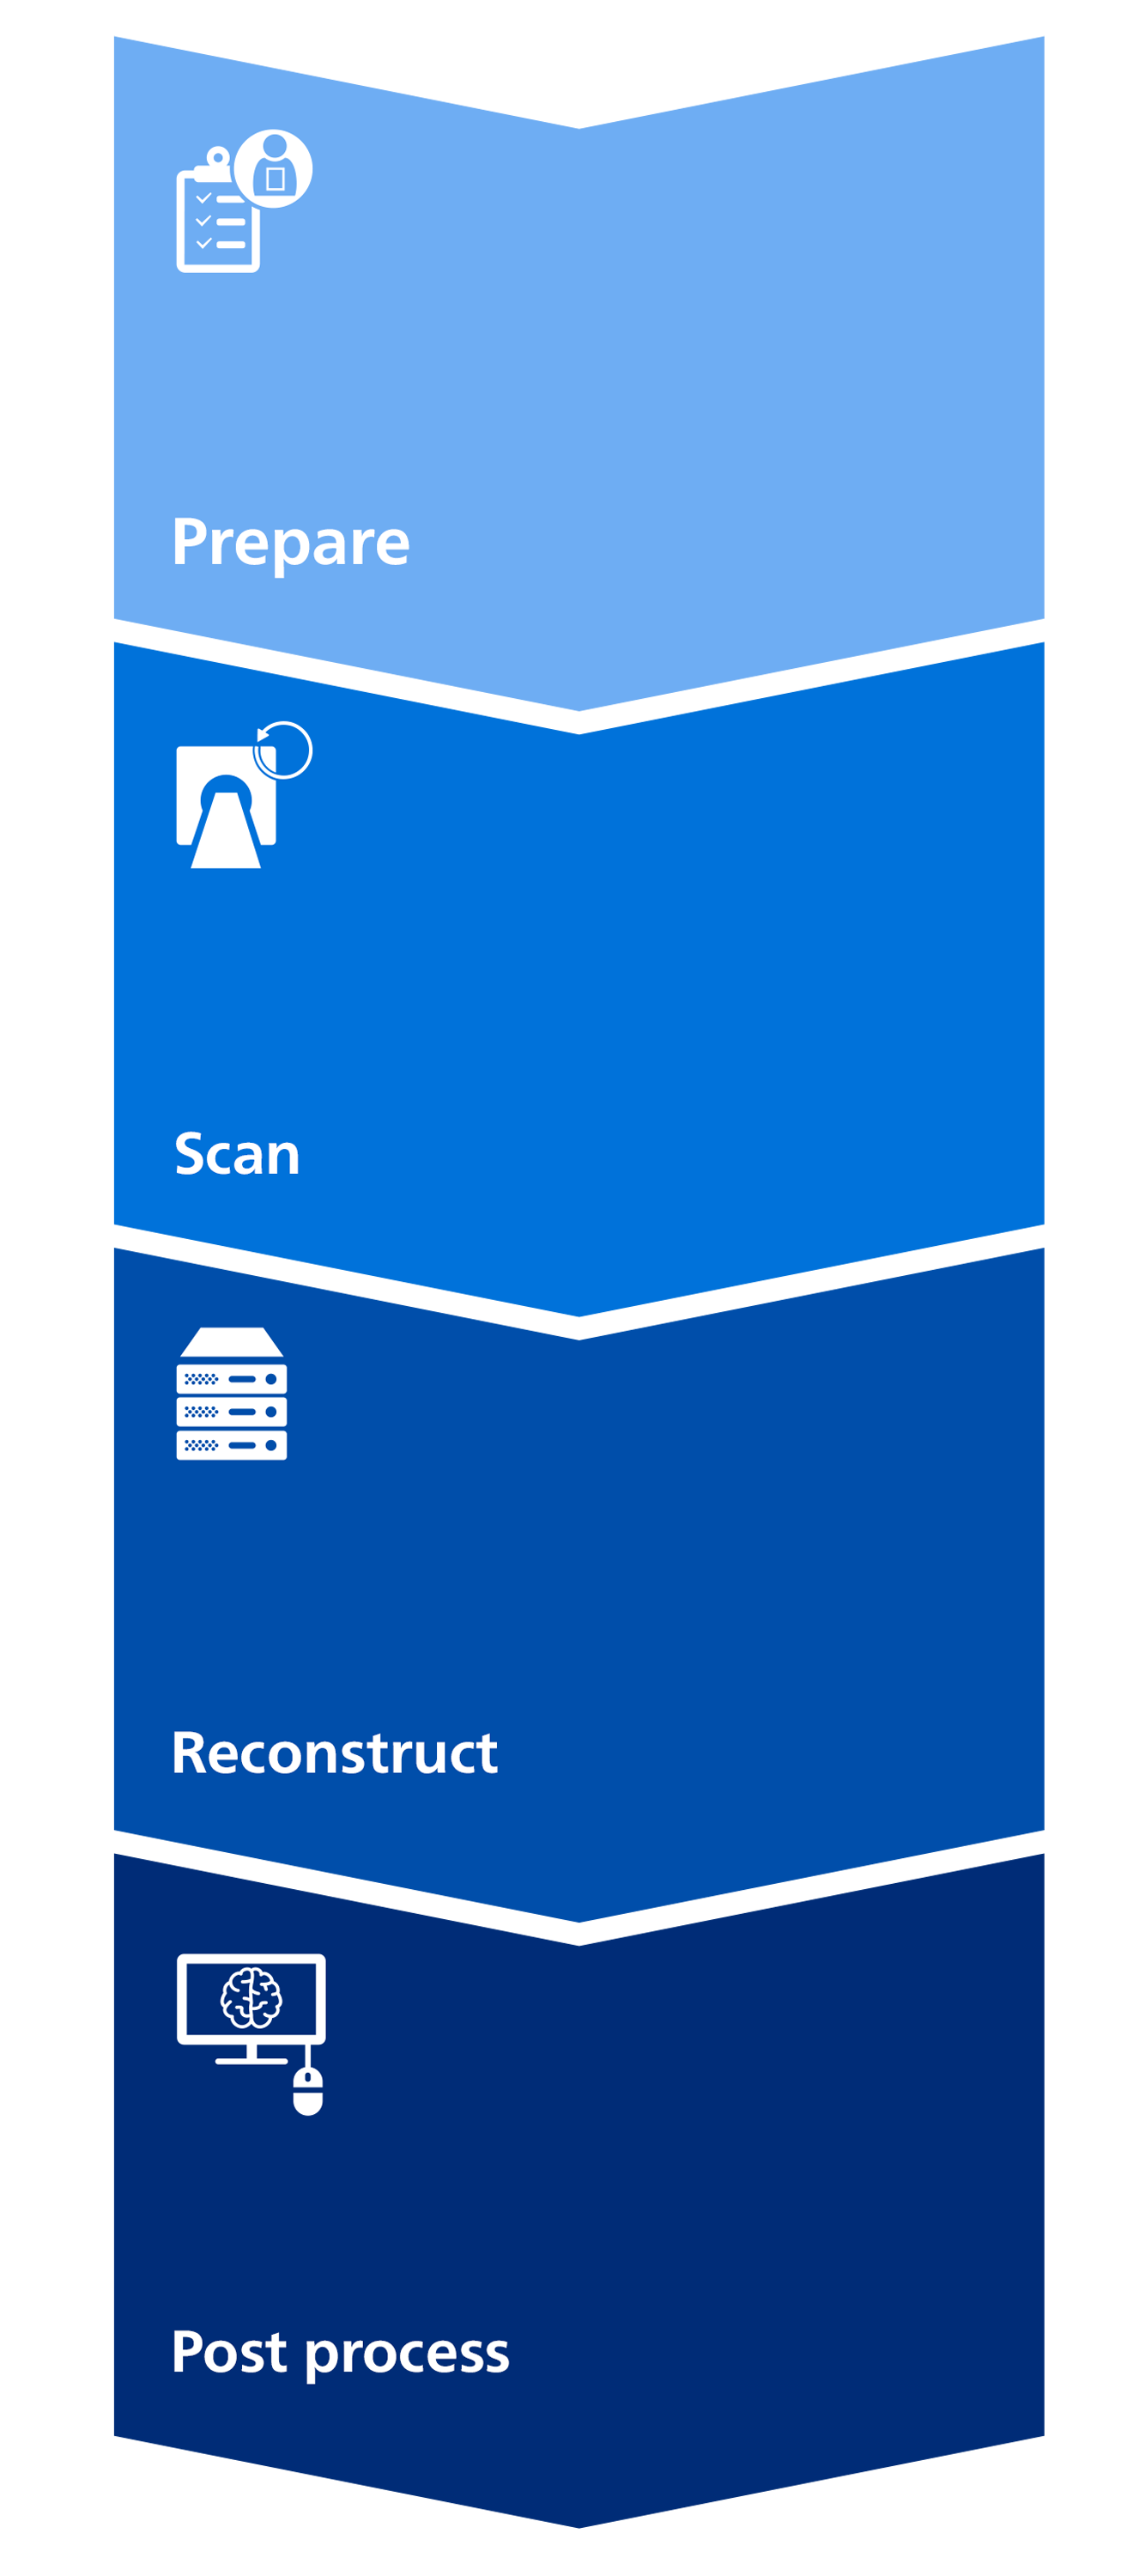

See how CT Smart Workflow assists your team at every step

See how Smart Workflow assists your team with smarter workflow at every step